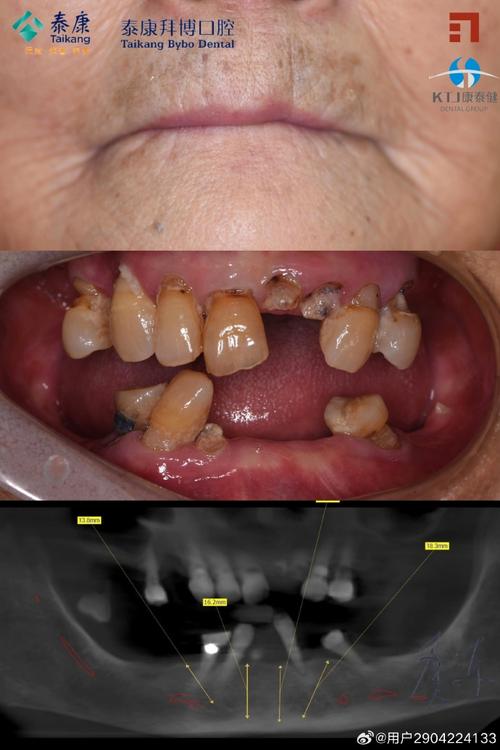

种植牙的治疗流程在国外已标准化,通常分为五个阶段,首先是术前检查与评估,医生会通过口腔检查、CBCT影像、血液化验等方式,判断患者的口腔状况(如牙槽骨高度、密度、宽度)、全身健康状况(如是否有糖尿病、高血压等系统性疾病),排除种植禁忌症,其次是方案设计,结合患者需求(如单颗牙缺失、多颗牙缺失、全口无牙)和骨质条件,选择合适的种植体类型、直径及长度,并确定是否需要植骨、上颌窦提升等附加手术,第三是手术植入,在局部麻醉下,通过小切口翻瓣(或微创不翻瓣),将种植体植入牙槽骨内,手术时间通常为30分钟-2小时(根据种植数量复杂程度而定),第四是骨整合期,种植体植入后需与牙槽骨结合,一般需3-6个月(下颌骨通常比上颌骨愈合快),期间可佩戴临时修复体不影响美观,最后是修复阶段,骨结合完成后,安装基台并取模,制作牙冠(全瓷冠、烤瓷冠或金属冠),试戴调整后完成最终修复。

从技术发展来看,国外种植牙领域始终处于创新前沿,20世纪50年代,瑞典学者Branemark教授提出的“骨结合”理论奠定了现代种植牙的基础,此后欧美国家持续推动技术迭代,如今数字化种植已成为主流,通过CBCT(锥形束CT)进行三维影像分析,结合口内扫描获取数字化模型,医生可在电脑上模拟种植体植入位置、角度及深度,利用3D打印技术制作手术导板,实现精准微创种植,将手术误差控制在0.1毫米以内,部分国家还引入动态导航系统,进一步提升种植手术的安全性与成功率,在材料方面,钛及钛合金因具有良好的生物相容性和机械强度,仍是种植体的主流选择,而近年来氧化锆等全瓷材料因美观度高、无金属过敏风险,也逐渐应用于前牙区种植修复。